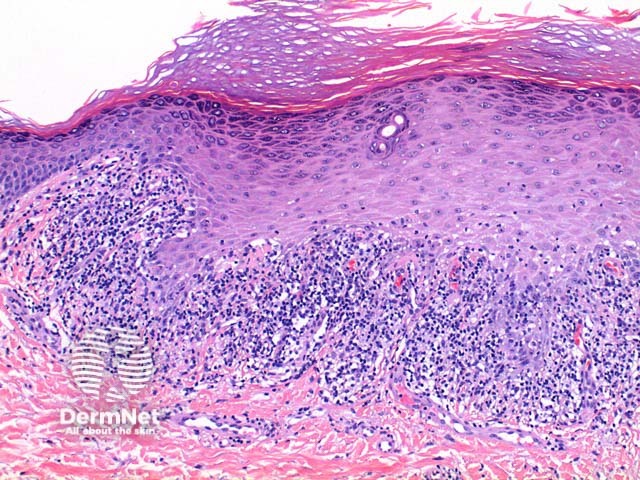

Scanning power view of lichen planus shows a lichenoid reaction pattern (Figure 1) characterised by the combination of degeneration of the basal layer of the epidermis and a band like lymphocytic infiltrate obscuring the dermoepidermal junction. There is irregular epidermal hyperplasia forming a characteristic saw-tooth appearance with wedge-shaped hypergranulosis (Figures 1 and 2). The basal layer of the epidermis exhibits vacuolar degeneration with typically prominent necrosis of individual keratinocytes (Figure 3). The inflammatory infiltrate is chiefly lymphocytic and forms a dense band in the superficial dermis (Figure 4).

Figure 1